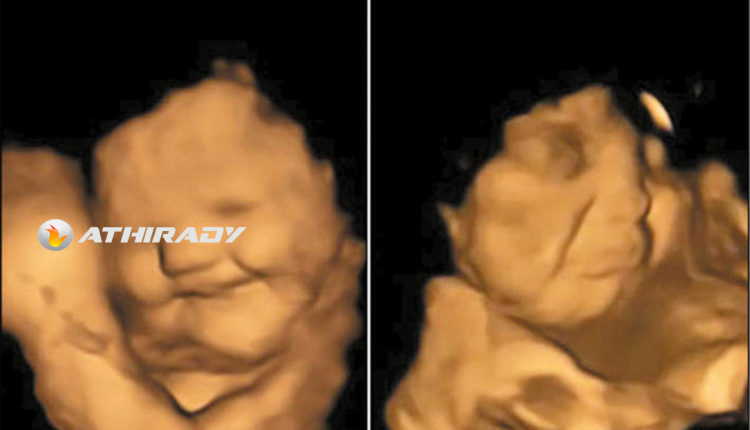

கேரட் கேப்சூல் சாப்பிட்ட கர்ப்பிணியின் கருக்குழந்தை புன்னகைப்பதையும், கீரை கேப்சூல் உட்கொண்ட கர்ப்பிணியின் கருக்குழந்தை சிணுங்கி அழுவதுபோல காணப்படுவதையும் காணலாம்.

அதில் கேரட் கேப்சூல் விழுங்கிய கர்ப்பிணிகளின் கருக்குழந்தைகள் புன்னகைப்பதையும், பரட்டைக்கீரை கேப்சூலை சாப்பிட்ட கர்ப்பிணிகளின் கருக்குழந்தைகள் சிணுங்கி அழுவதுபோல காணப்படுவதையும் கண்டுபிடித்தனர். அதாவது, கேரட் கருக்குழந்தைகளுக்கு பிடித்து, அவர்களைப் புன்னகைக்க வைத்திருக்கிறது. பரட்டைக்கீரை அவர்களை சிணுங்க வைத்திருக்கிறது. கவனியுங்கள். இதில் கருக்குழந்தைகள் எதையும் சாப்பிடவில்லை. அவர்களின் தாய்கள்தான் அவற்றை சாப்பிட்டு இருக்கிறார்கள்.